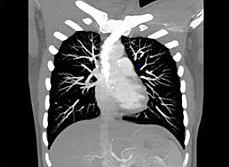

• Lung Cancer Testing

Lung Cancer Testing

Men at age 55 or older should talk to a health care provider to talk about smoking history and whether to get tested. one test would be a low dose CT scan. This test takes cross images of your body. Instead of like an x ray that only takes one picture. This CT scan can take many. It is very important to talk to your health care provider about getting tested because even if you do not smoke you could still be about second hand smoke which is almost just as bad.